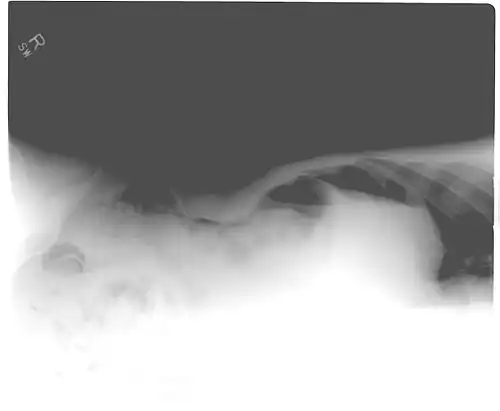

The Cupola sign is seen when air is accumulated under the central tendon of the diaphragm.[23]